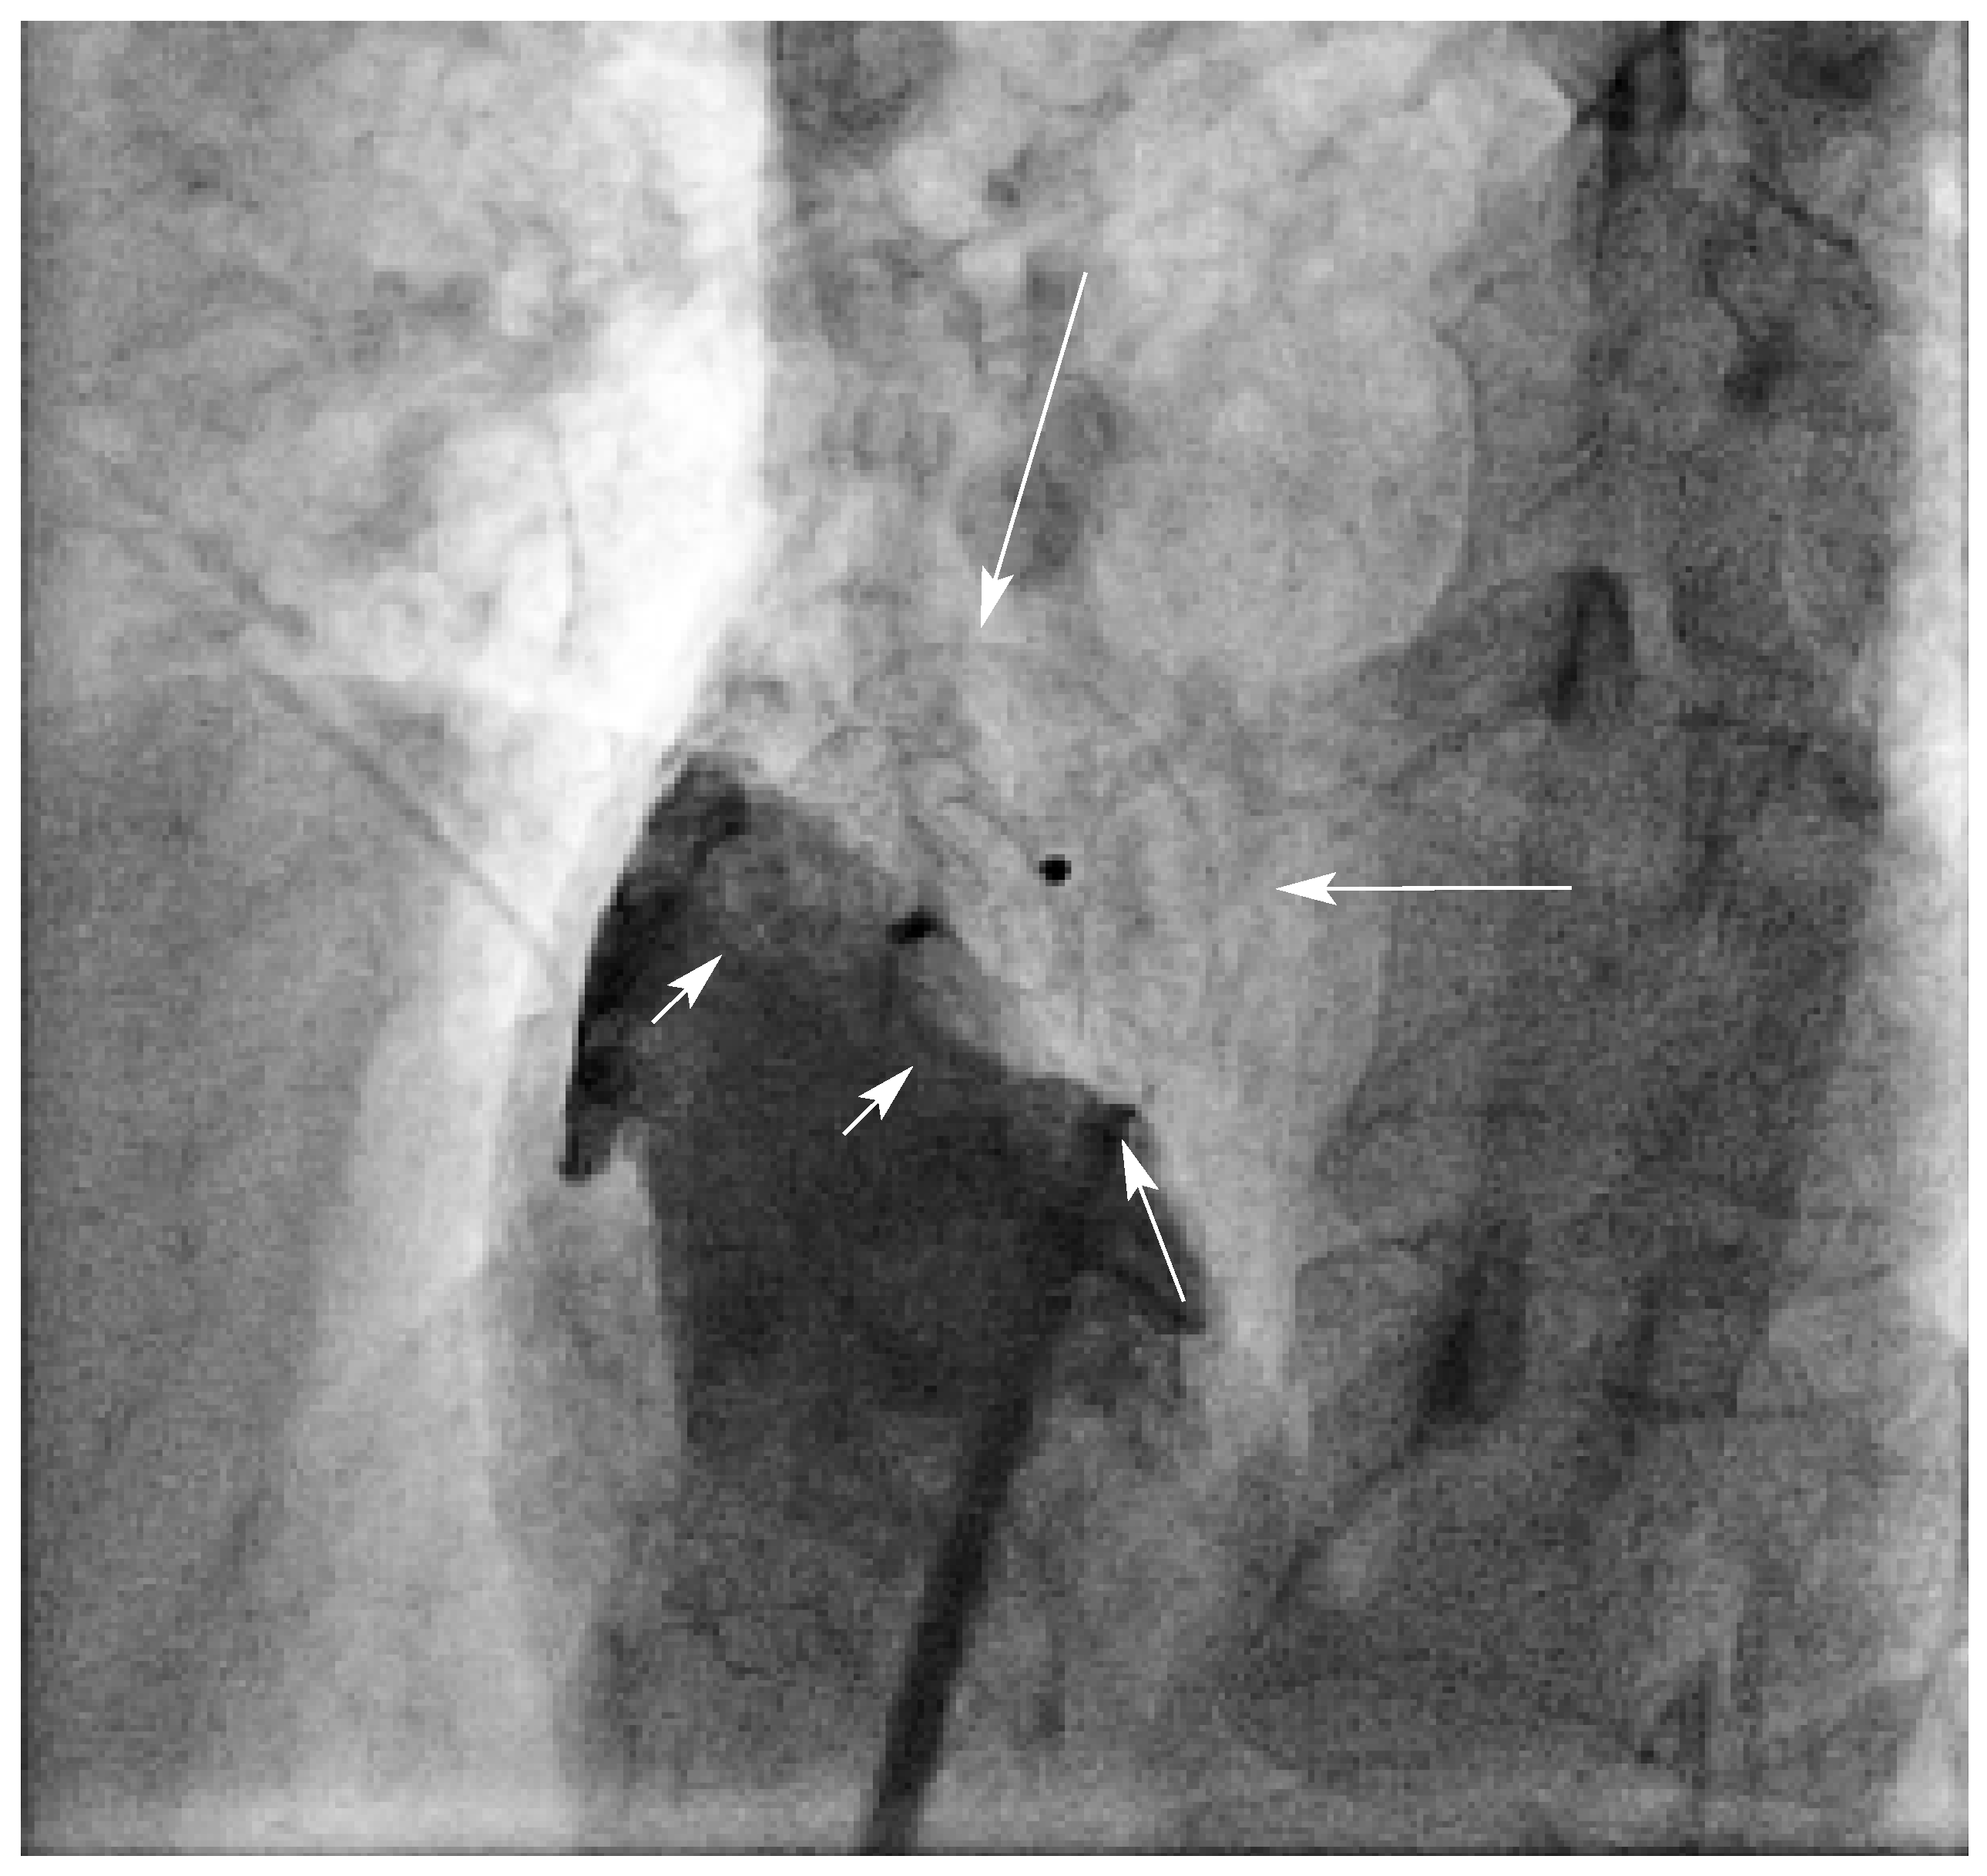

Abbildung 2. Kein Rest-Shunt nach Plazierung des Verschluss-Schirmes (Pfeile). Kontrastmittel-Injektion in den rechten Vorhof (kleine Pfeile).

Im ersten halben Jahr 2004 hat der Autor bei 11 Patienten ein OFO perkutan nach den oben erwähnten Kriterien verschlossen (Abb. 2). Davon litten 4 Patientinnen (38-, 39-, 44und 47jährig) seit Jahren an Migräne, wobei die Indikation zum OFO-Verschluss nicht aufgrund der Migränesymptomatik gestellt wurde. Sowohl unmittelbar vor und nach Plazierung des Amplatzer-PFO-Occluders™ als auch anlässlich der nach 3–6 Monaten durchgeführten Kontrollen wurden keine Rest-Shunts, weder mittels «Bubbles»-Kontrastnoch mittels Farbdoppler-Untersuchung nachgewiesen (Abb. 3).